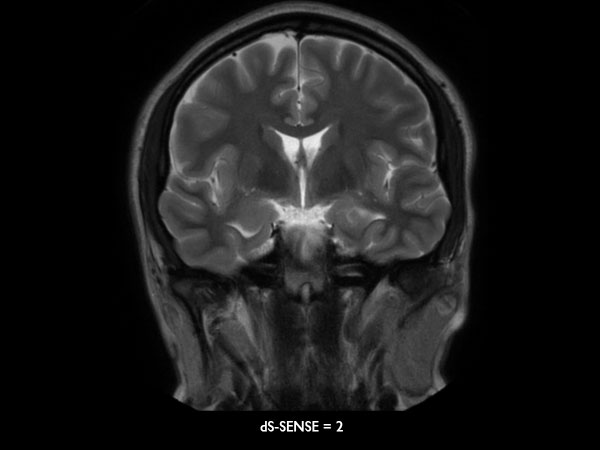

Coronal T2w MultiVane XD